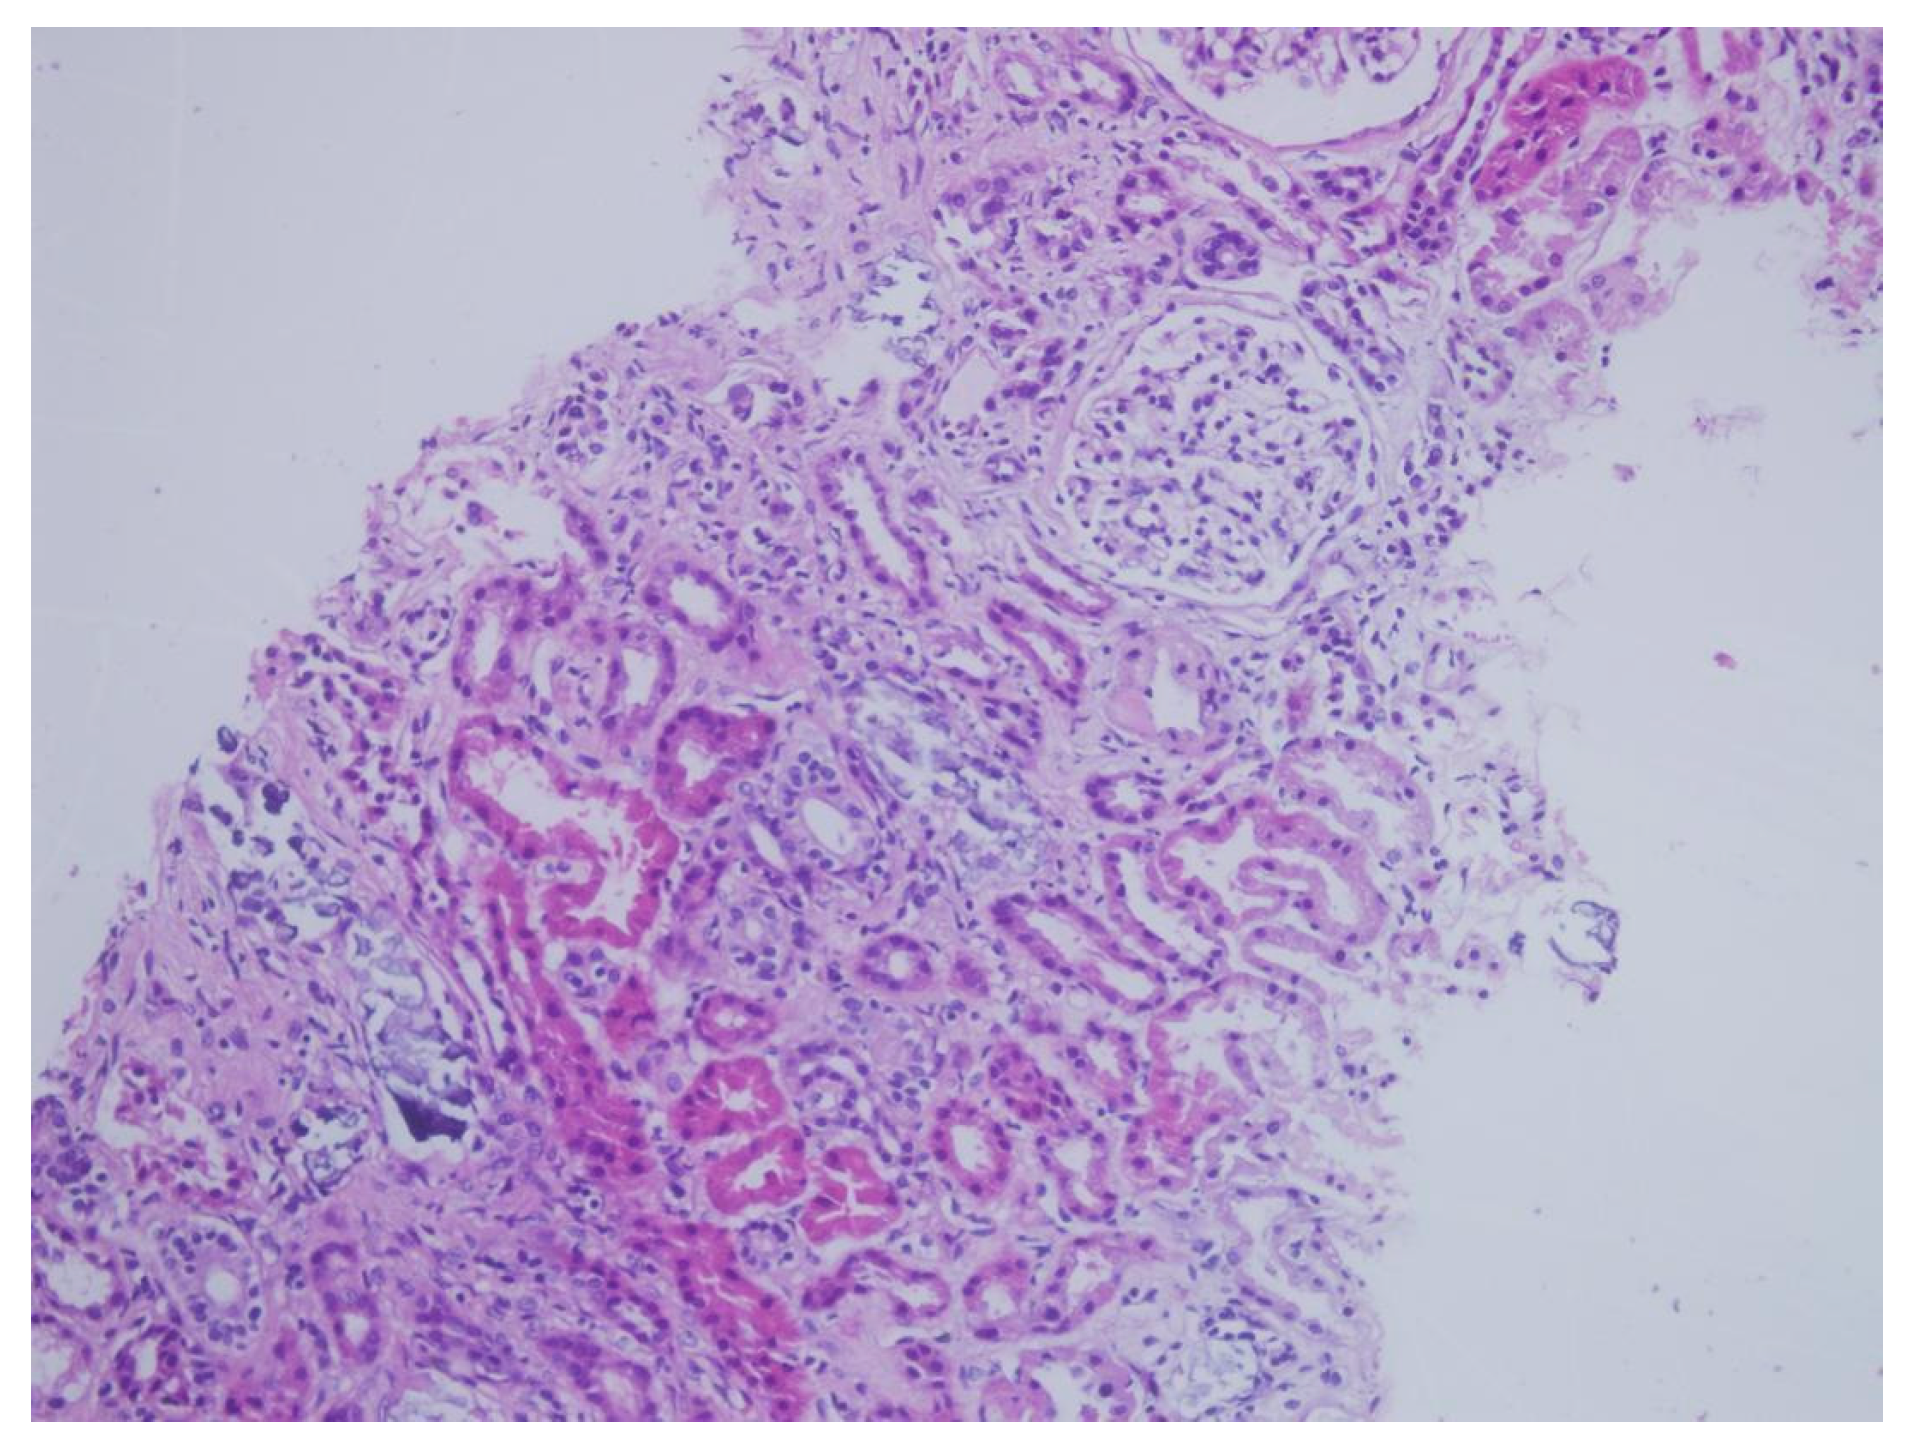

| Tubulointerstitial deposition | + | + | + | + | + | + | + | + | + |

| Tubular necrosis | − | − | + | − | − | − | − | − | − |

| von Kossa staining | + | + | + | + | + | + | + | + | + |